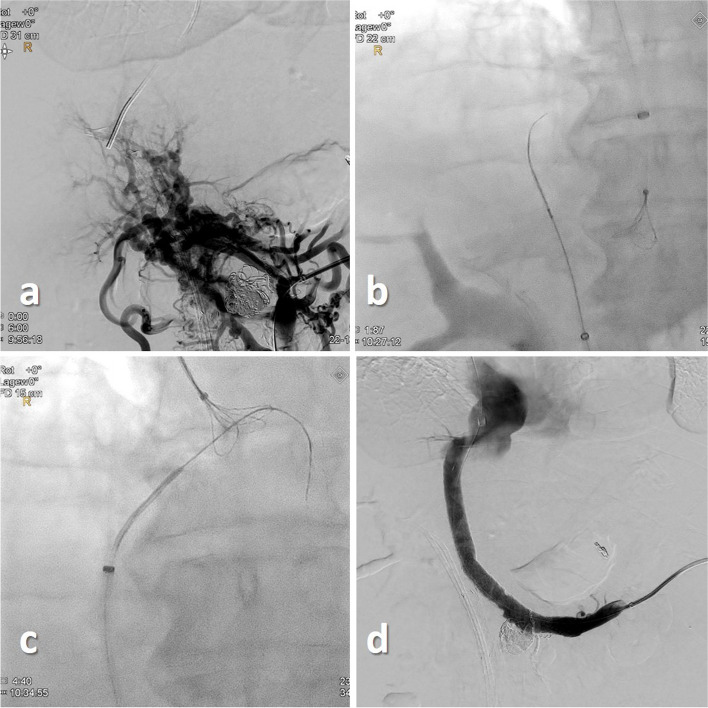

Background: Three patients with portal hypertension and gastrointestinal bleeding due to non-cirrhotic portal vein thrombosis were treated with portal venous recanalization transjugular intrahepatic portosystemic shunt (PVR-TIPS) via a trans-splenic access.

Main body: A "bottoms-up" retrograde puncture of the right hepatic vein was performed using a re-entry catheter to gain access to the right hepatic vein. In all patients a successful retrograde puncture of the right hepatic vein was achieved, thereby restoring the splenoportal tract.

Conclusion: Our cases present an alternative approach to treat chronic portal vein thrombosis expanding the possibilities of the PVR-TIPS procedure.